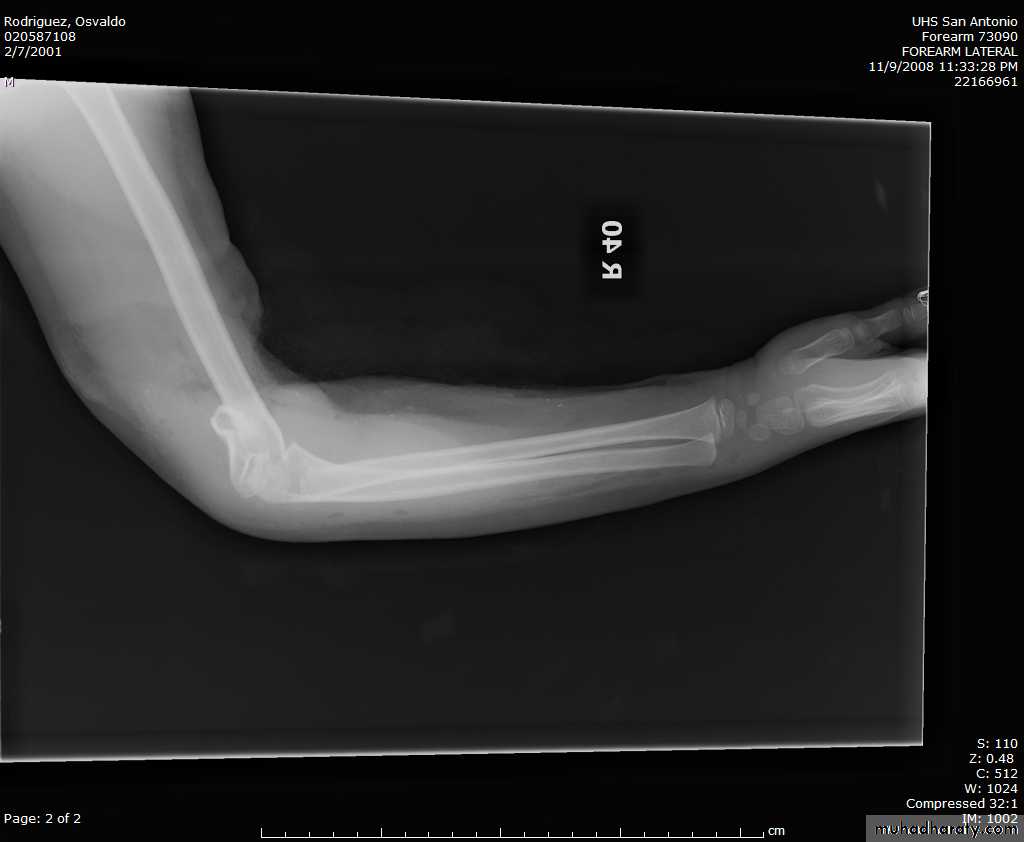

8 y.o. rolled over on an ATV

with mild closed head injuryClinical appearance

Only N-V deficit:

Anterior interosseous n. function weak

Radial A.

FCR Musc.Imaging Studies

How are we going to stabilize this boy’s fracture?